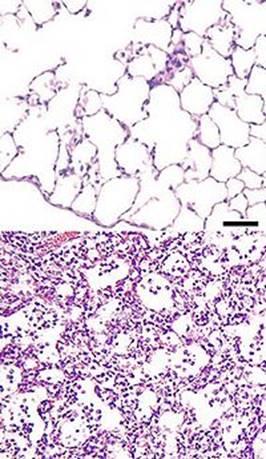

Рис. 1: Схема гипостатической пневмонии у человека

Рис.2. Гипостатическая пневмония. Микрокартина.